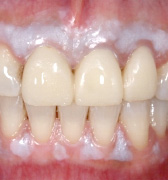

前歯にファイバーコアを入れ、オールセラミッククラウンを被せた症例

歯内療法をした後、グラスファイバー系のコア(土台)を入れました。利点として、歯根破折を起こしにくい、光の透過性が天然歯に近い、金属を使わないので歯肉に影ができないなど、美しく、自然な仕上がりとなります。